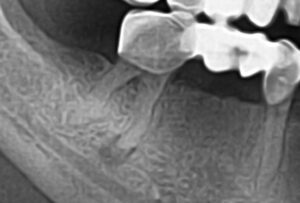

Зуб интактный или разрушен кариозным процессом, изменен в цвете. Кариозный дефект сообщается с полостью зуба, зондирование полости, а также устьев каналов безболезненное, температурные пробы не выражены, реакция на перкуссию слабо болезненная. Слизистая оболочка в окружности зуба и в области переходной складки не изменена или слегка гиперемирована. Порог электровозбудимости свыше 100 мкА. Рентгенологически наблюдается деструкция верхушечного отдела периодонта и окружающей костной ткани округлой или овальной формы размером до 0,5 см с четкими контурами.